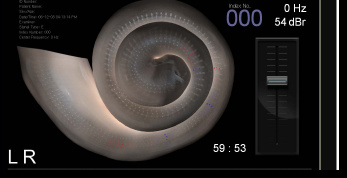

꿀팁!!!

끝까지 읽어주신 데 대한

감사의 마음으로 드리는 팁입니다.

#이명 치료를 위해서 어느 병원이나

어느 한의원을 가시더라도

그냥 무턱대고 치료 받겠다고 하지 마시고

#이명 탐색기는 있는지 어떠한 원리로

이명을 치료하고 치료가 되는지

치료 사례는 얼마나 되고

보여 줄 수 있는지를 반드시

팩트체크 하신 후에 결정하시기 바랍니다.

이명탐색기(REVE-134)사진임

답을 제대로 못하거나 이명탐색기가 없다면

좀 고민해 보겠다하고

얼른 나오시기 바랍니다.

#이명 탐색기 없이 #이명을 고친다는 것은

칼없이 정육점을 운영한다는 것 내지는

시력 측정장비 없이 안경점을 운영한다는

것과 같은 논리이기 때문입니다

꼭 기억하시고 실천하시기 바랍니다